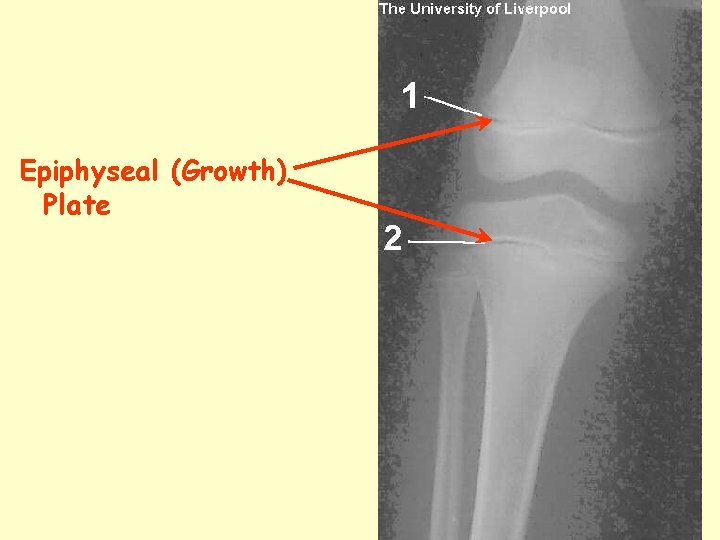

Parts of a Bone • Epiphyses – ends • Diaphysis – shaft • Epiphysial line – Where they meet – AKA growth plate • Medulary Cavity – Contains yellow bone marrow

Epiphyseal (Growth) Plate